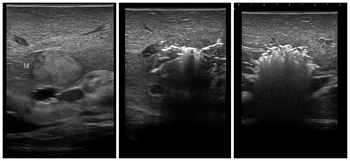

消融后术中超声造影检查,显示肿瘤消融彻底,无活性

8月23日,在麻醉科,超声科及手术室团队的配合下,为患者成功实施了肝脏右后叶切除术+肝病损微波消融术,手术非常成功。患者第2天可自行下地活动,第7天拔除了腹腔的3根引流管,术后第8天顺利出院。